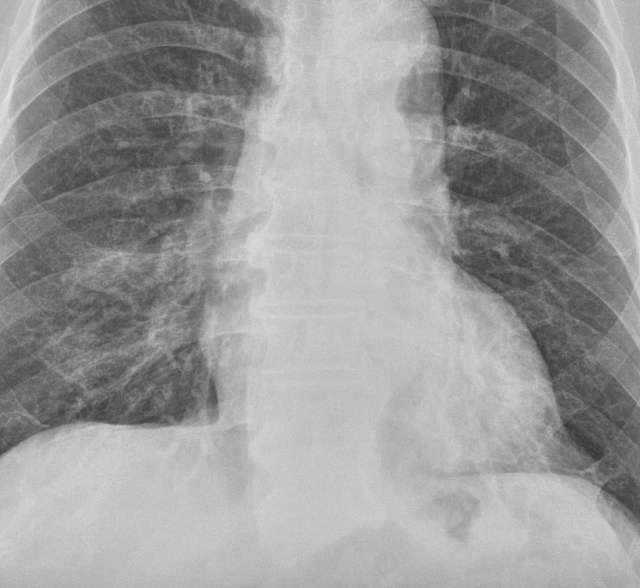

별다른 임상정보 없이 위와 같은 가슴사진이 판독할 리스트에 떳다고 해봅시다. 의학적인 지식이 전무한 일반인이라면, 당연히 이게 뭔지, 뭘 봐야 하는지조차 아무런 감이 없으실 겁니다. 바로 이런 단계를 투자영역에서는 “호구”라고 부를 수 있을겁니다.

사실 이 환자는 동네 의원에서 폐렴이 의심된다고 해서 내과로 입원한 분입니다. 당연히 폐렴의 가능성을 제일 먼저 확인해야 겠지요. 위 영상에서 뭔가 이상소견이 보이시는지요? 의대생이 졸업을 하기 전에 가슴사진에 대해 공부를 할 때 제일 중요하게 강조되는 개념이 “실루엣 징후”입니다. 사실, 의대생이라도 이 실루엣징후라는 것을 “제대로” 공부했다면 이 사진에서 무엇이 문제라는 걸 금방 알 수 있습니다. 어찌 되었든 간에 이게 흉부단순촬영 영상이라는 것, 그리고 환자의 임상증상을 볼 때 왜 이 사진을 촬영한 것인지 전후사정을 이해할 수 있다면 적어도 “뭔가를 좀 아는” 상태라고 할 수 있습니다. 투자영역으로 따지면 호구까지는 아니고 이제 첫걸음을 떼고 앞으로 나아갈 준비가 되있는 “초보”단계로 볼 수 있습니다.